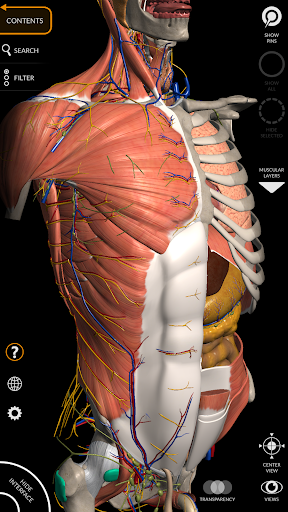

"Anatomy 3D Atlas" cho phép bạn nghiên cứu giải phẫu người theo cách dễ dàng và tương tác.

Thông qua giao diện đơn giản và trực quan, bạn có thể quan sát mọi cấu trúc giải phẫu từ mọi góc độ.

Các mô hình giải phẫu 3D đặc biệt chi tiết và có kết cấu lên đến độ phân giải 4k.

Việc phân chia theo vùng và chế độ xem được xác định trước giúp quan sát và nghiên cứu các bộ phận hoặc nhóm hệ thống riêng lẻ và mối quan hệ giữa các cơ quan khác nhau.

• Hệ thống cơ xương

• Hệ thống tim mạch

• Hệ thống thần kinh

• Tùy chọn ẩn hoặc cô lập một hoặc nhiều mô hình đã chọn

• Bộ lọc để ẩn hoặc hiển thị từng hệ thống

• Hình dung các cơ qua các lớp từ lớp nông đến lớp sâu nhất